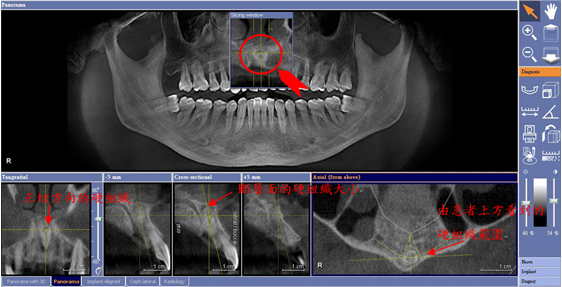

透過3D影像,可有效測量牙根與上顎鼻竇的距離

透過CT成像,將可發現口腔組裡的不明硬組織